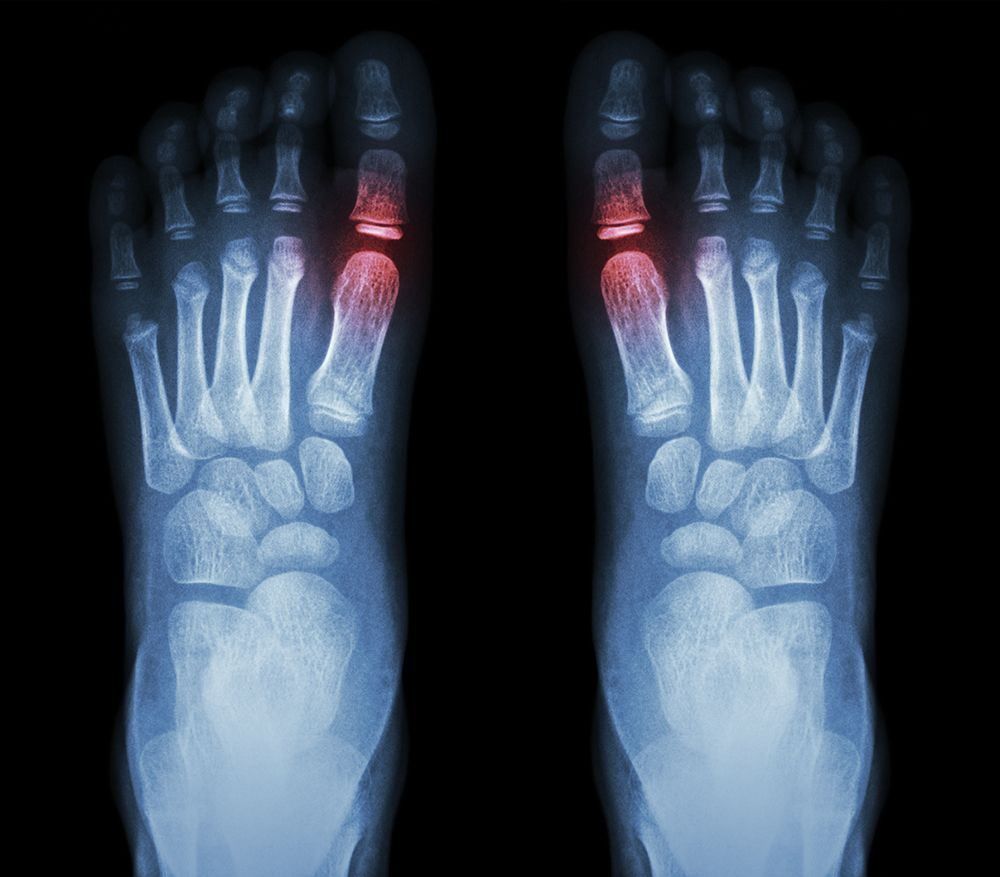

At The Podiatry Center, we use the latest technology to deliver precise diagnoses and effective treatment for a wide range of foot and ankle conditions. Our advanced tools include digital X rays, diagnostic ultrasound, shockwave therapy, MLS laser therapy, Swift wart treatment, and 3D scanning for custom orthotics. By combining innovative technology with individualized care, we provide faster relief, improved outcomes, and long term support for lasting foot and ankle health.